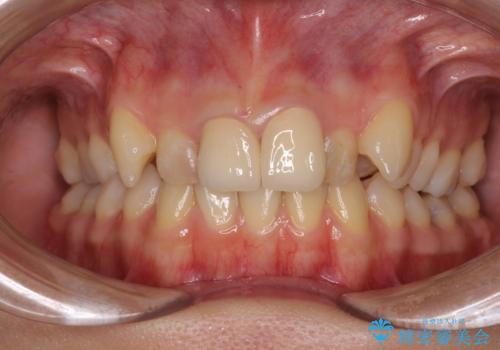

変色したバランスの悪い前歯をオールセラミッククラウンで自然な口元に

矯正治療を行うかどうかは相当悩まれており、セラミッククラウンが装着されるまで、本当に良かったのかと心配されていましたが、とてもきれいな口元に仕上がり、大変満足していただけました。